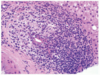

What is a granuloma?

- Organised collection of activated macrophages (epithelioid macrophages)

- Secretory macrophages

- Associated with infections e.g. TB, leprosy, fungal infection